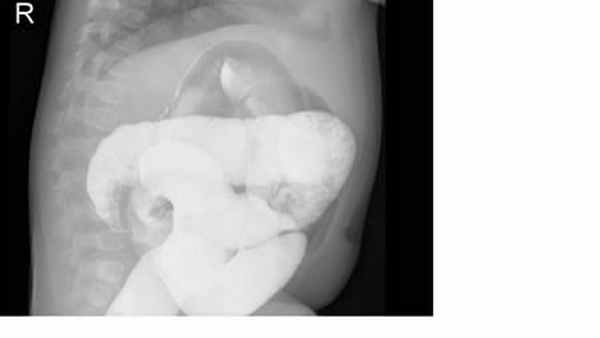

На рисунках 4 и 5 представлена картина кишечной инвагинации при рентгенологическом исследовании.

Рис. 4. Ирригограмма при тугом наполнении взвесью сульфата бария – симптом «клешней рака»